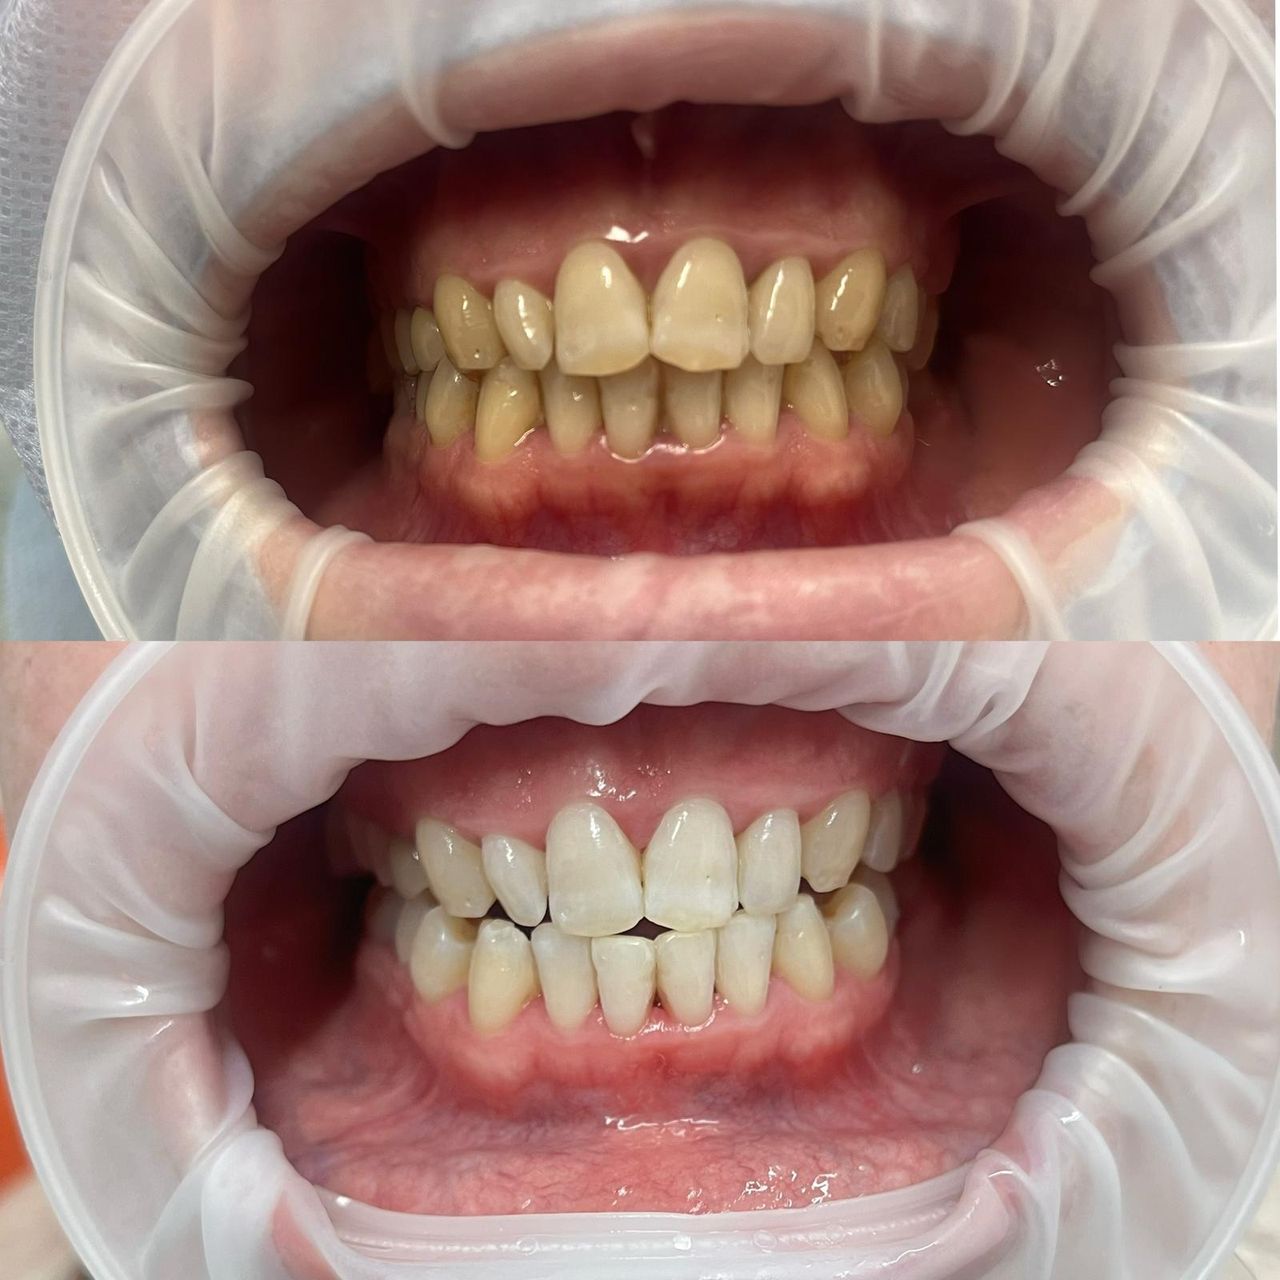

Zdjęcia i filmy